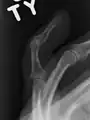

El diagnóstico generalmente se basa en el estudio de los síntomas, apoyado por Radiografías .

Un dedo en martillo sin una fractura asociada